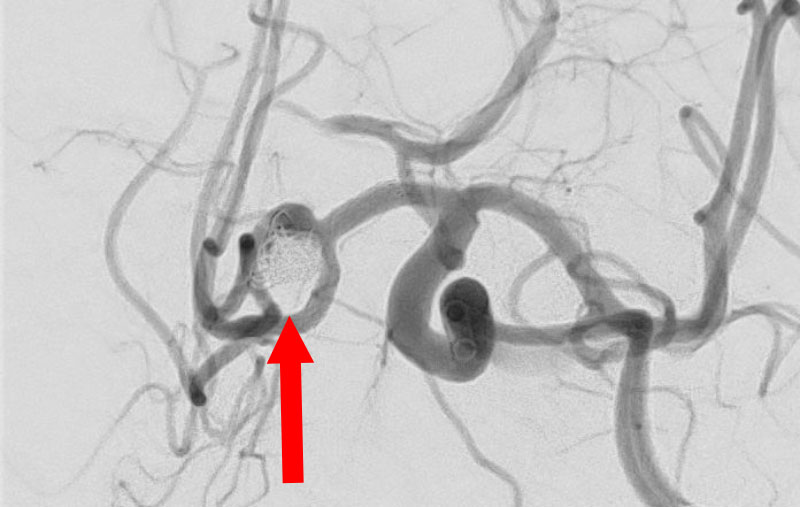

No.1593 手術前